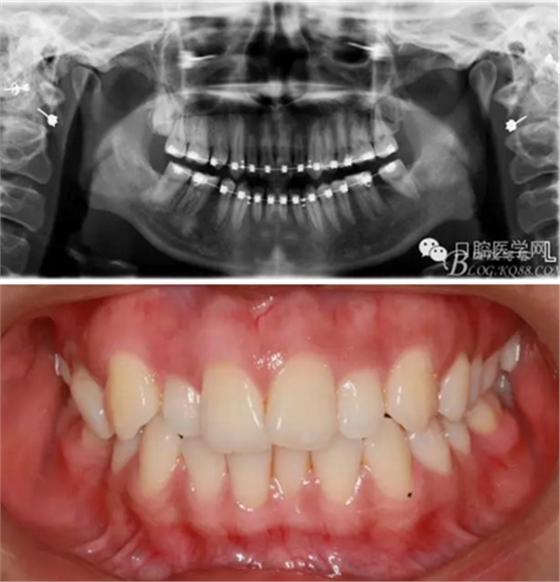

37,45缺失后,鄰牙近中移動(dòng)占據(jù)了部分牙位;患者要求減少治療費(fèi)用,不做種植修復(fù),那怎么協(xié)調(diào)右側(cè)的咬合關(guān)系?

15是根管治療過的牙齒,只好忍痛舍去......

在滿足功能的前提下,退而求其次...有時(shí)候,正畸醫(yī)生不得不妥協(xié)。